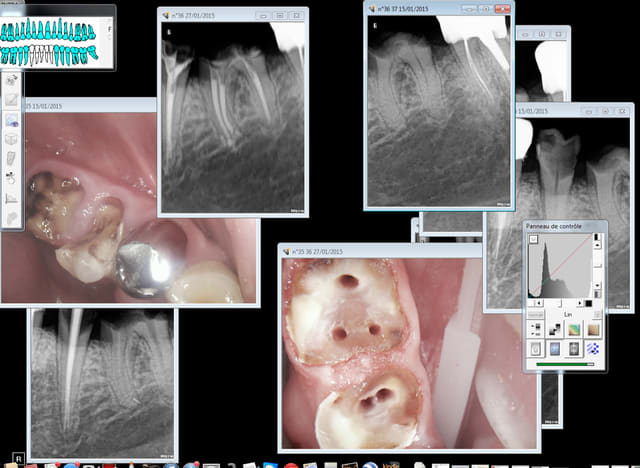

Moi je fais. Mais j ai des aides optiques..je vais retrouver une radio d un traitement de correspondant que j ai fait il y a peu tu me diras si c est ressemblant

traitement fait juste avec loupes. l'ouverture de la chambre et trouver les entrées canalaires ca a été coton mais faisable..1h30 de traitement tout de même

Mme durif annette 1 azvr6d - Eugenol

Mme durif annette 4 kdtmtm - Eugenol

manquait celle ci désolé

Mme durif annette 2 makpln - Eugenol